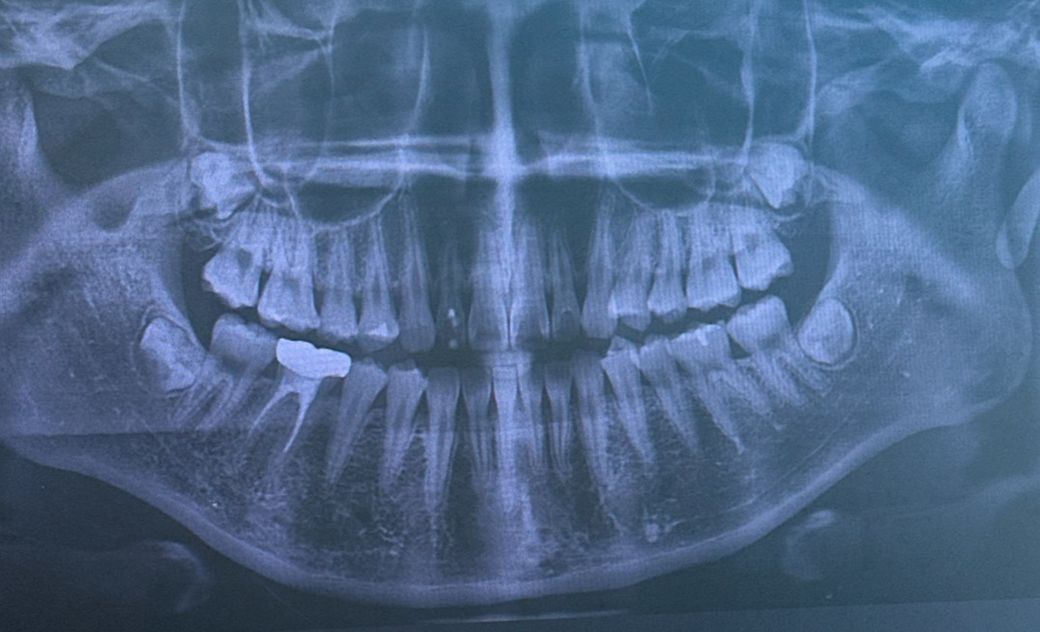

다 자라지 않은 사랑니 발치 가능한가요?

사랑니 발치 하고 싶은데 의사가 뼈깍아야한다고 안해준다는데 앞 치아가 흐트러지는거 같고 그냥 빨리 빼버리고 싶은데 이거 못빼나요?

• 1번 째 사진

다 자라지 않은 사랑니도 발치를 하는 것은 가능하지만 앞치아가 흐트러지진 않으니 조금 더 뒤에 빼셔도 됩니다.

발치는 가능하지만 아직 발치를 해야될 필요성은 없는것같습니다. 발치를 하게되면 잇몸도 절개후 잇몸뼈 삭제도 필요해 보입니다.

1. 비보험이라 일반 발치보다 더 비쌉니다

2. 뼈 깍아야 할 상황 맞습니다

3. 형성중인 사랑니로 치열이 틀어지진 않습니다

4. 원한다면 할 순 있지만 굳이 싶네요